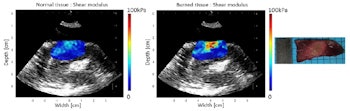

Shear modulus maps of the left ventricle, before (left) and after (center) ablation, with SWE and HIFU performed through an esophagus. The mean shear modulus increased from 21.2 ± 3.3 kPa to 73.8 ± 13.9 kPa in the central-8-mm-diameter zone. A photograph of the gross pathology section is shown on the right.

In an example ablated zone in the chicken breast, the mean shear modulus increased from 4.8 ± 1.1 kPa before ablation to 20.5 ± 10.0 kPa after treatment. In the left atrium, the mean shear modulus increased from 12.2 ± 4.3 to 30.3 ± 10.3 after ablation. In one of the left ventricle ablations, the researchers inserted an ex vivo esophagus around the transducers and performed HIFU and imaging through the esophagus. Here, the mean stiffness increased from 21.2 ± 3.3 to 73.8 ± 13.9 kPa in the central region.